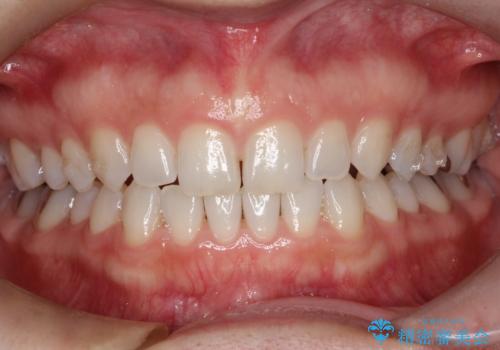

- 前歯の正中離開(すきっ歯)の改善を希望され来院された患者様です。

初診時の歯並びの状態としては、上顎中切歯間に1mm程の隙間があり、その他に見た目に関して気になるような問題点はない状態でした。

インビザライン(マウスピース)にて上顎のみの矯正治療を行いました。

見た目、嚙み合わせ及び、治療期間や施術内容に大変ご満足いただきました。